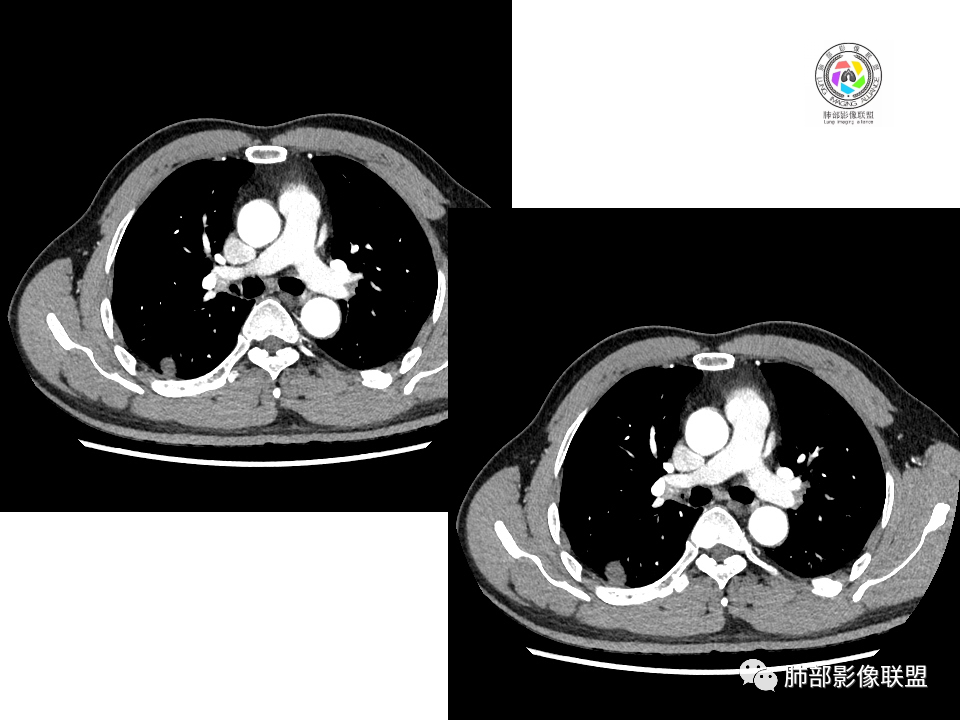

男性,49岁,体检发现,右肺下叶背段胸膜下见肿块,边界清楚,边缘光滑,胸膜下脂肪间隙存在,有分叶,无毛刺,均匀强化,内无坏死,右肺下叶血管束间不规则实性结节,边界清楚,无明显强化,中叶少许斑片状高密度影,纵隔未见明显增大淋巴结,考虑良性病变。

2.右肺下叶背段胸膜下块影,边界清楚光整,上下极见磨玻璃晕,未见明显分叶毛刺和棘状突起,未见胸膜凹陷或胸壁侵入。密度均匀,轻度不均匀强化。未见支气管进入。

3.右肺中叶外侧段胸膜下散在小片影,磨玻璃密度为主,边界不清,支气管相关。符合炎性特征!

4.右肺下叶基底段支气管血管束旁小结节影,边界清楚,强化不明显。注意,这结节在“遥远的”基底段。